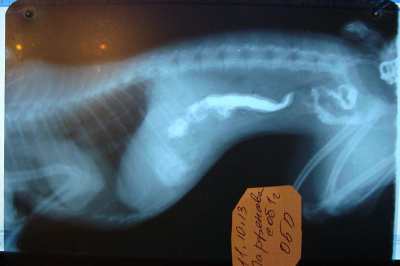

Вирусный энтероколит у щенков - фото презентация